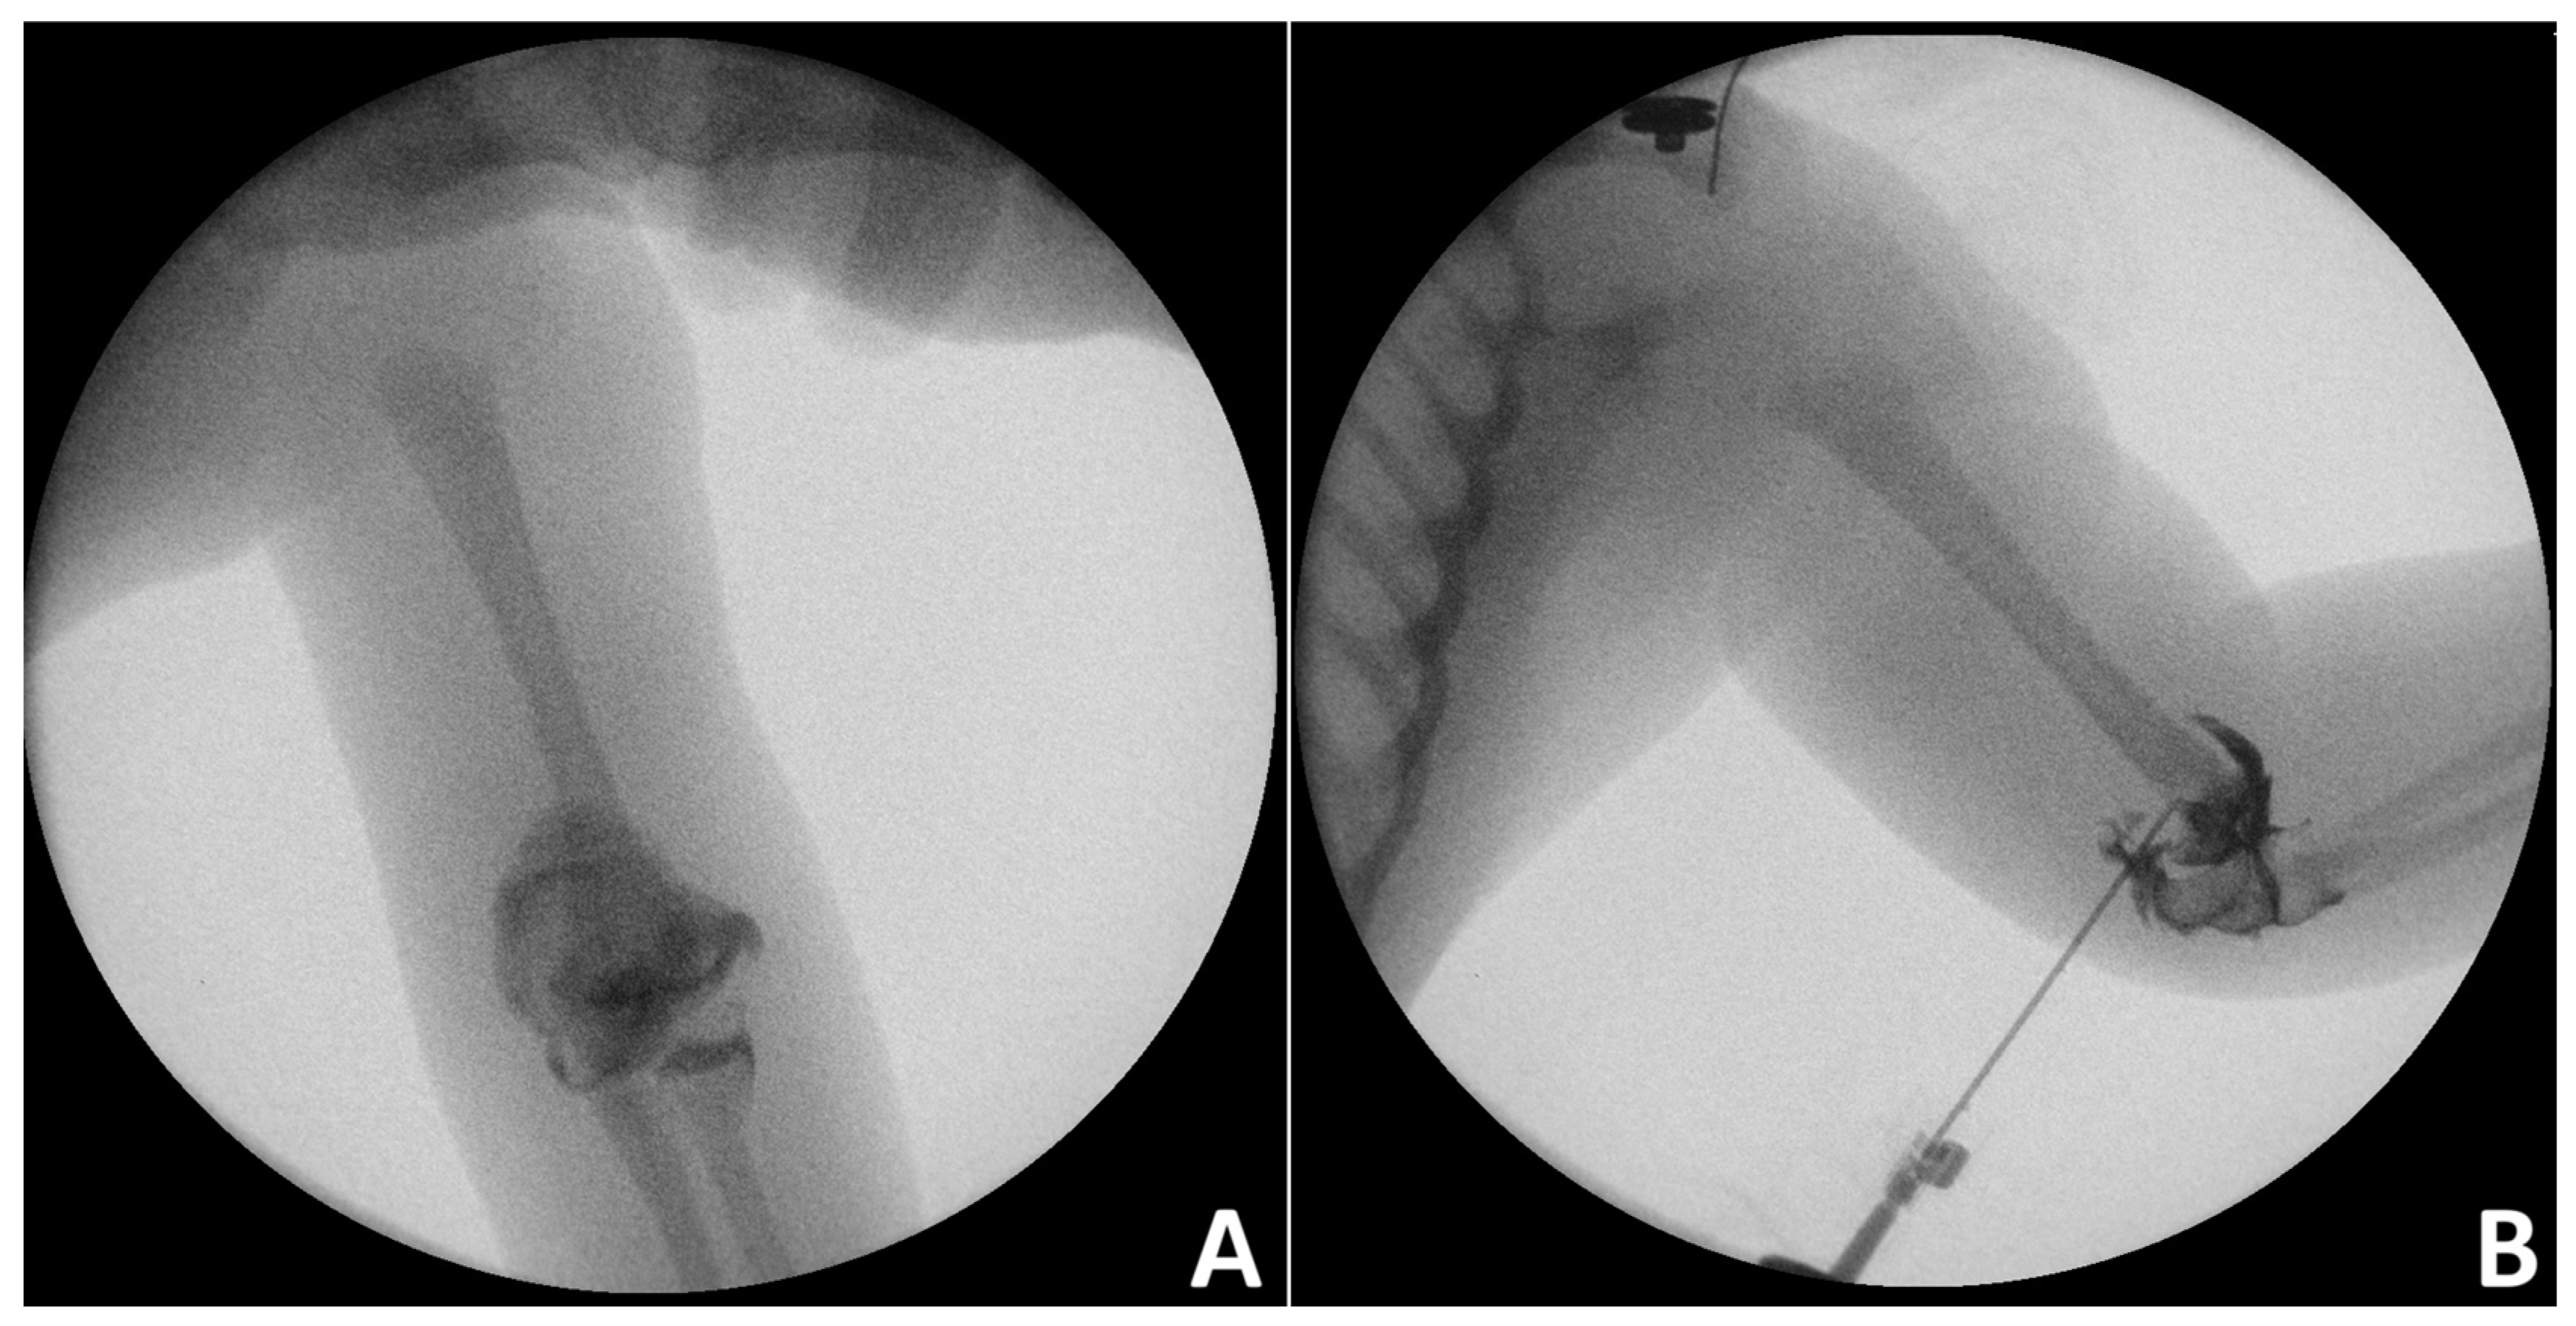

In infants and toddlers, elbow arthrogram is usually performed during CRPP of DHPS to improve anatomic reduction in the distal humerus (Figure 3) [28].

However, Chou et al. [29] suggested that, instead of intraoperative arthrogram, fracture reduction could be safely evaluated by checking if the ulnar axis was within the boundaries of the medial and lateral humeral lines. The authors reported that the method was associated with decreased incidence of cubital varus deformity.